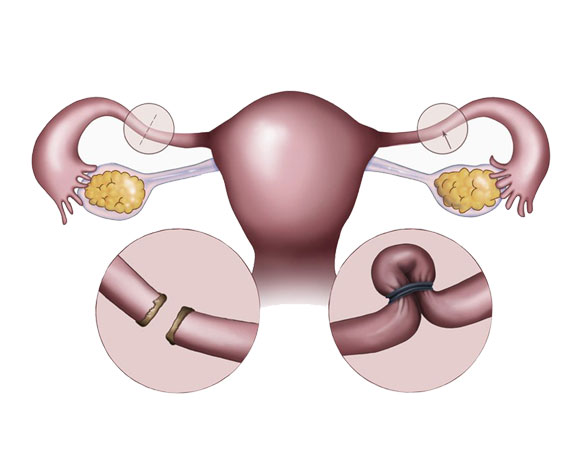

Myomların klinik bulguları genellikle lokalizasyonları ile ilişkilidir. Rahim kavitesinin içine doğru büyüyen submüköz myomlar, uzamış ve ağır kanamaya neden olurlar. Bu myomlar aynı zamanda gebe kalmak isteyen kadınlarda da problem yaratırlar. Subseröz myomlar ise rahimin dış kısmına doğru büyüyen myomlardır. Bazen mesaneye bası yaparak idrar ile ilgili şikayetlere neden olabilirler. Eğer rahmin arka tarafına doğru büyürlerse rektuma bası ile kabızlık, spinal sinirlere bası ile bel ağrısına neden olabilirler.

Myomlar, genellikle gebe kalmaya engel olmasalar bile yerleşim yerlerine bağlı olarak spermlerin rahim içine girişlerine ya da tüplerden geçişine engel olabilirler. Yine rahim iç tabakasına yerleşmiş olan myomlar embriyo gelişimini engelleyebilirler. Gebelikte ise myomlar sıklıkla karın ve kasık ağrısı şikayetine neden olurlar. Bazı nadir durumlarda ise düşük ya da erken doğuma sebebiyet verebilirler.

Myomlar, genellikle tedavi gerektirmezler fakat hastada aşırı kanama, anemi, ağrı ya da gebeliğe engel durum oluşturuyorlarsa cerrahi olarak çıkarılmaları gerekir.